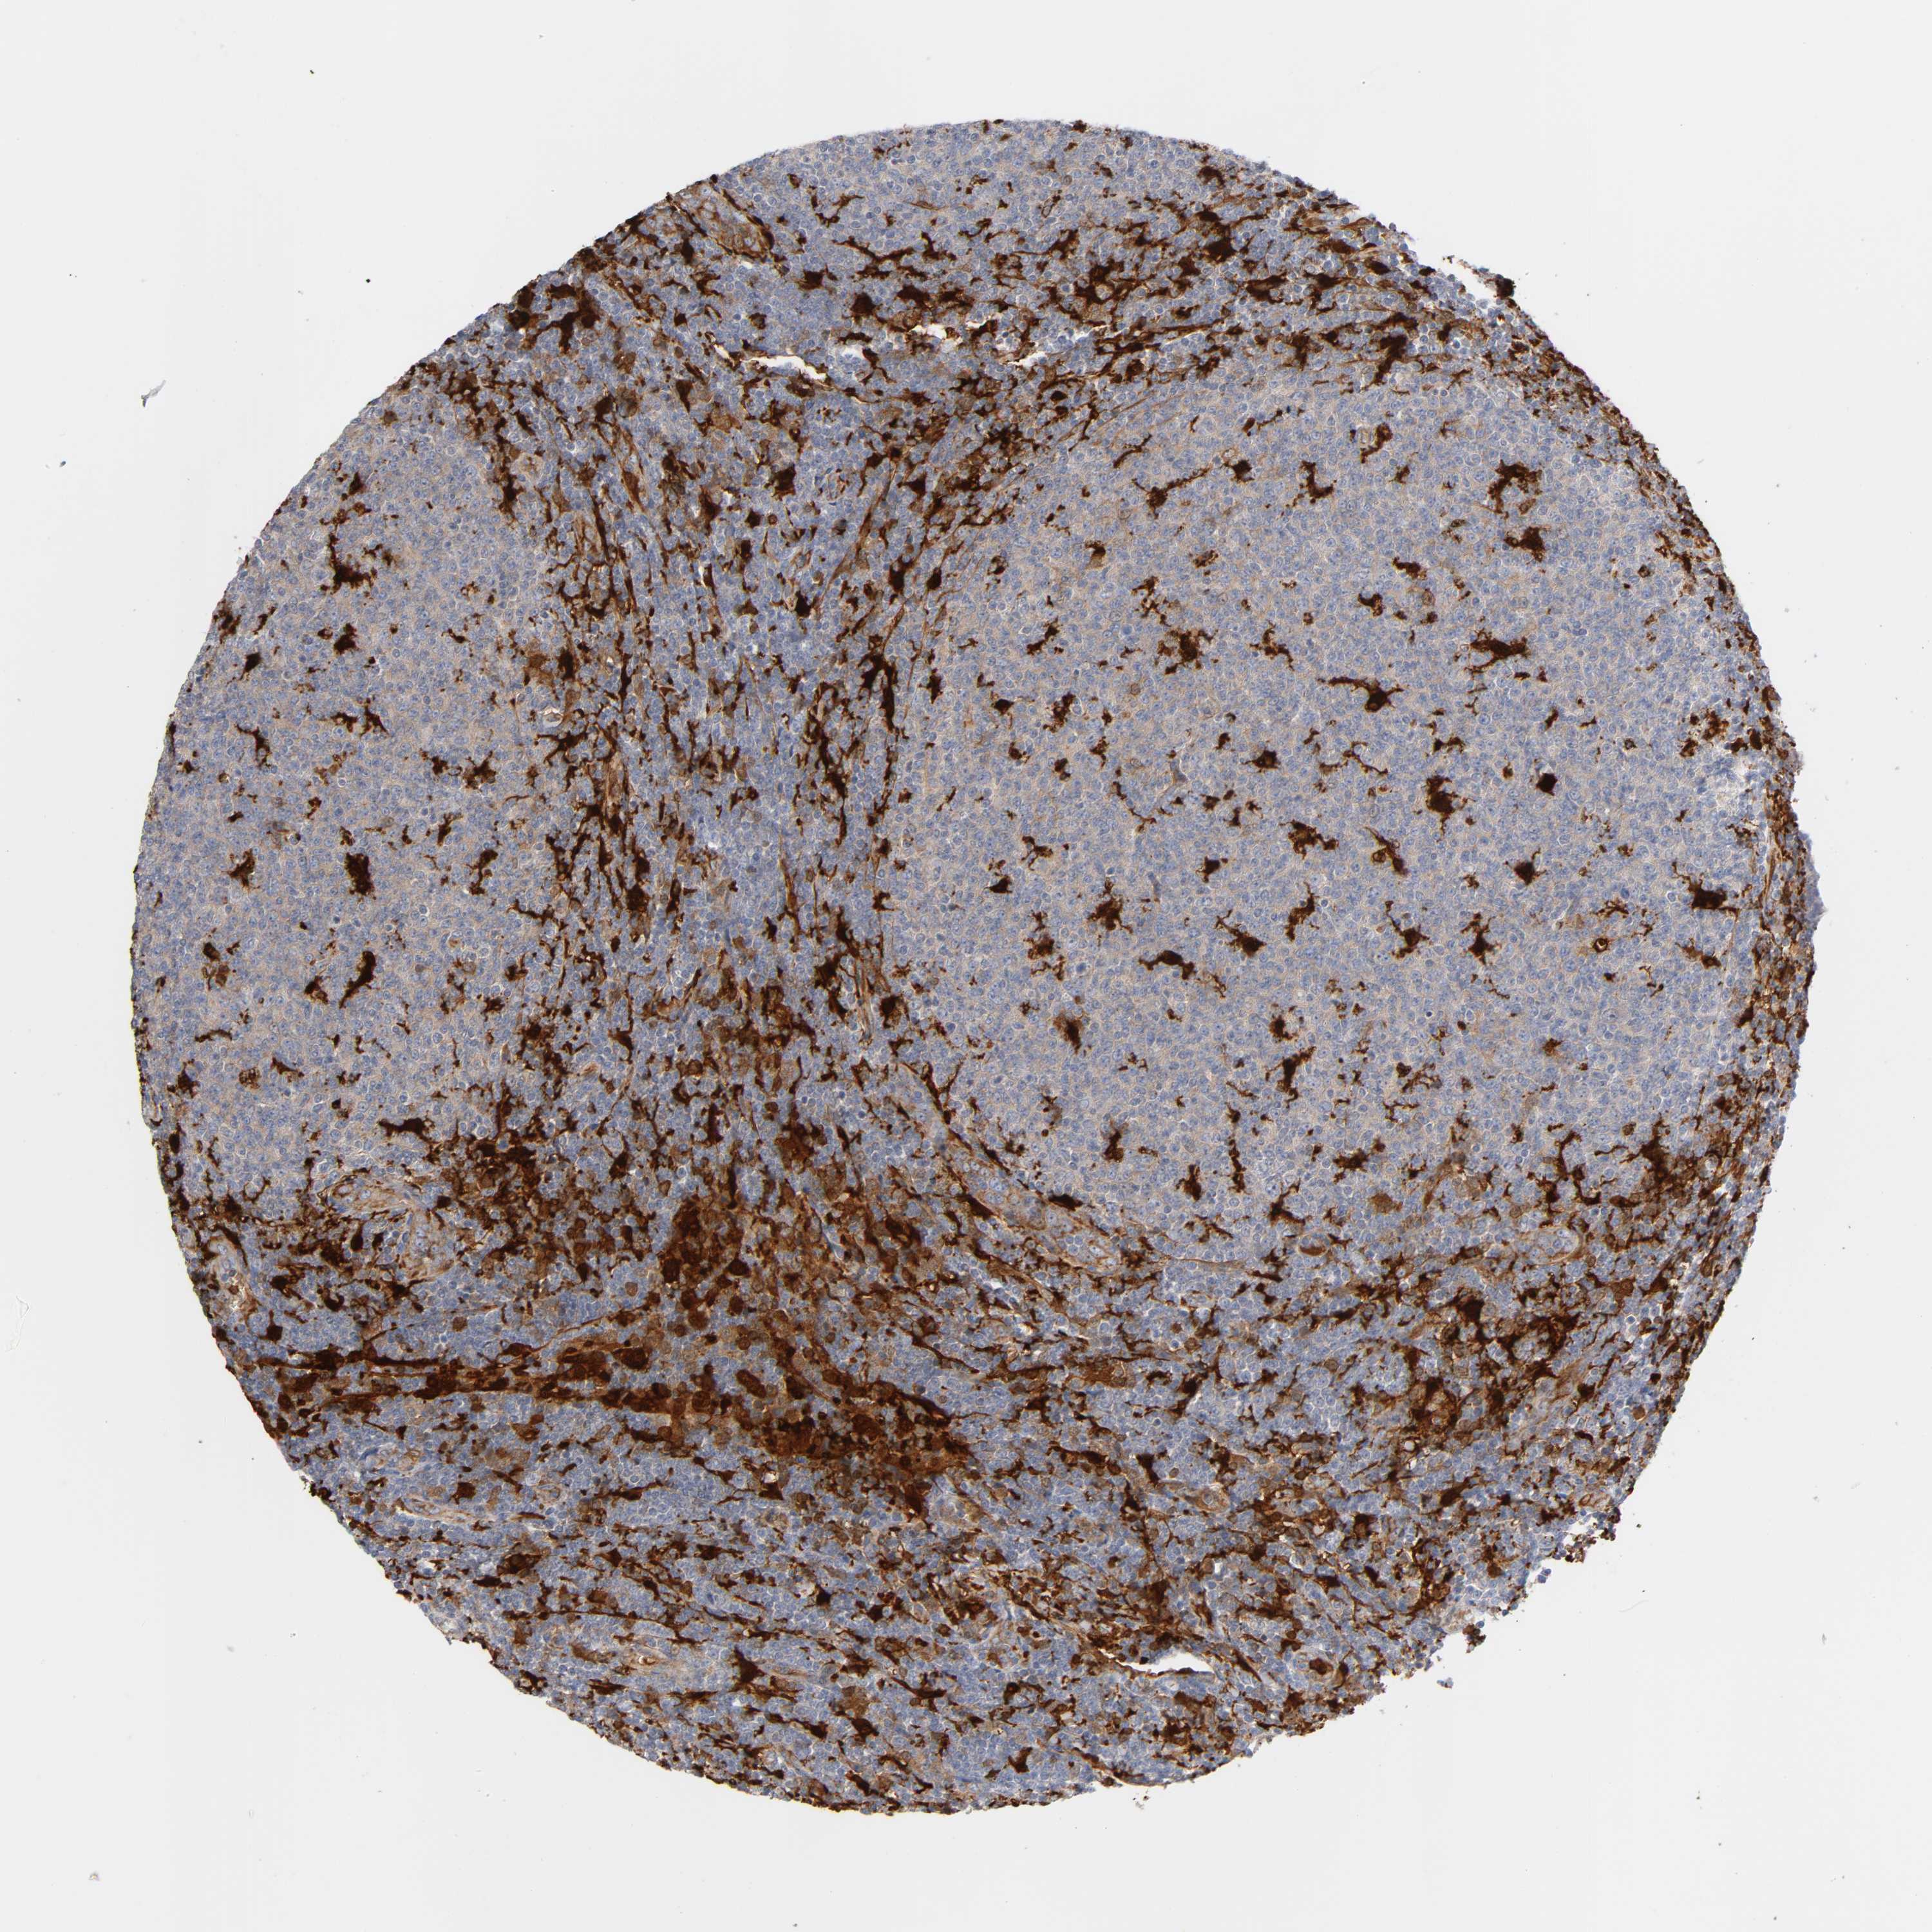

LYMPHOMA - Protein expressioni

A mouse-over function shows sample information and annotation data. Click on an image to view it in a full screen mode. Samples can be filtered based on level of antibody staining by selecting one or several of the following categories: high, medium, low and not detected. The assay and annotation is described here.

Antibody stainingi

Antibody staining in the annotated cell types in the current human tissue is reported as not detected, low, medium, or high, based on conventional immunohistochemistry profiling in selected tissues. This score is based on the combination of the staining intensity and fraction of stained cells.

Each image is clickable and will lead to virtual microscopy that enables deeper exploration of all samples and also displays staining intensity scores, fraction scores and subcellular localization as well as patient and tissue information for each sample.

Antibody HPA003980

Antibody CAB007772

Staining

High

Medium

Low

Not detected

Intensity

Strong

Moderate

Weak

Negative

Quantity

>75%

75%-25%

<25%

None

Location

Nuclear

Cytoplasmic/membranous

Cytoplasmic/membranous,nuclear

Hodgkin's disease, NOS

Malignant lymphoma, non-Hodgkin's type, High grade

Malignant lymphoma, non-Hodgkin's type, Low grade